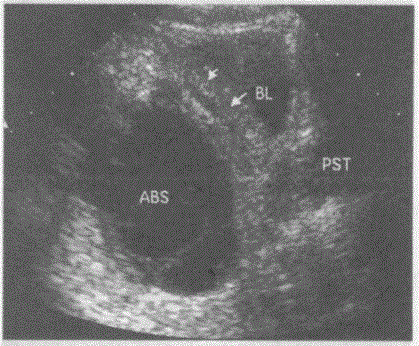

问题 临床资料:男,29岁,自诉发热、腹痛、腹坠胀不适十余天。 化验检查:血常规白细胞、中性粒细胞均增高。 超声综合描述:盆腔可见6.4cm×4.3cm无回声区,形态不规则,边界欠清晰,壁不均匀增厚,内透声不清亮,可见完整及不完整分隔,其旁膀胱壁增厚(箭头所指)。 超声提示:

选项 A.盆腔包裹性积液 B.盆腔脓肿膀胱壁受累增厚 C.肠梗阻肠腔积液 D.淋巴囊肿

答案 B